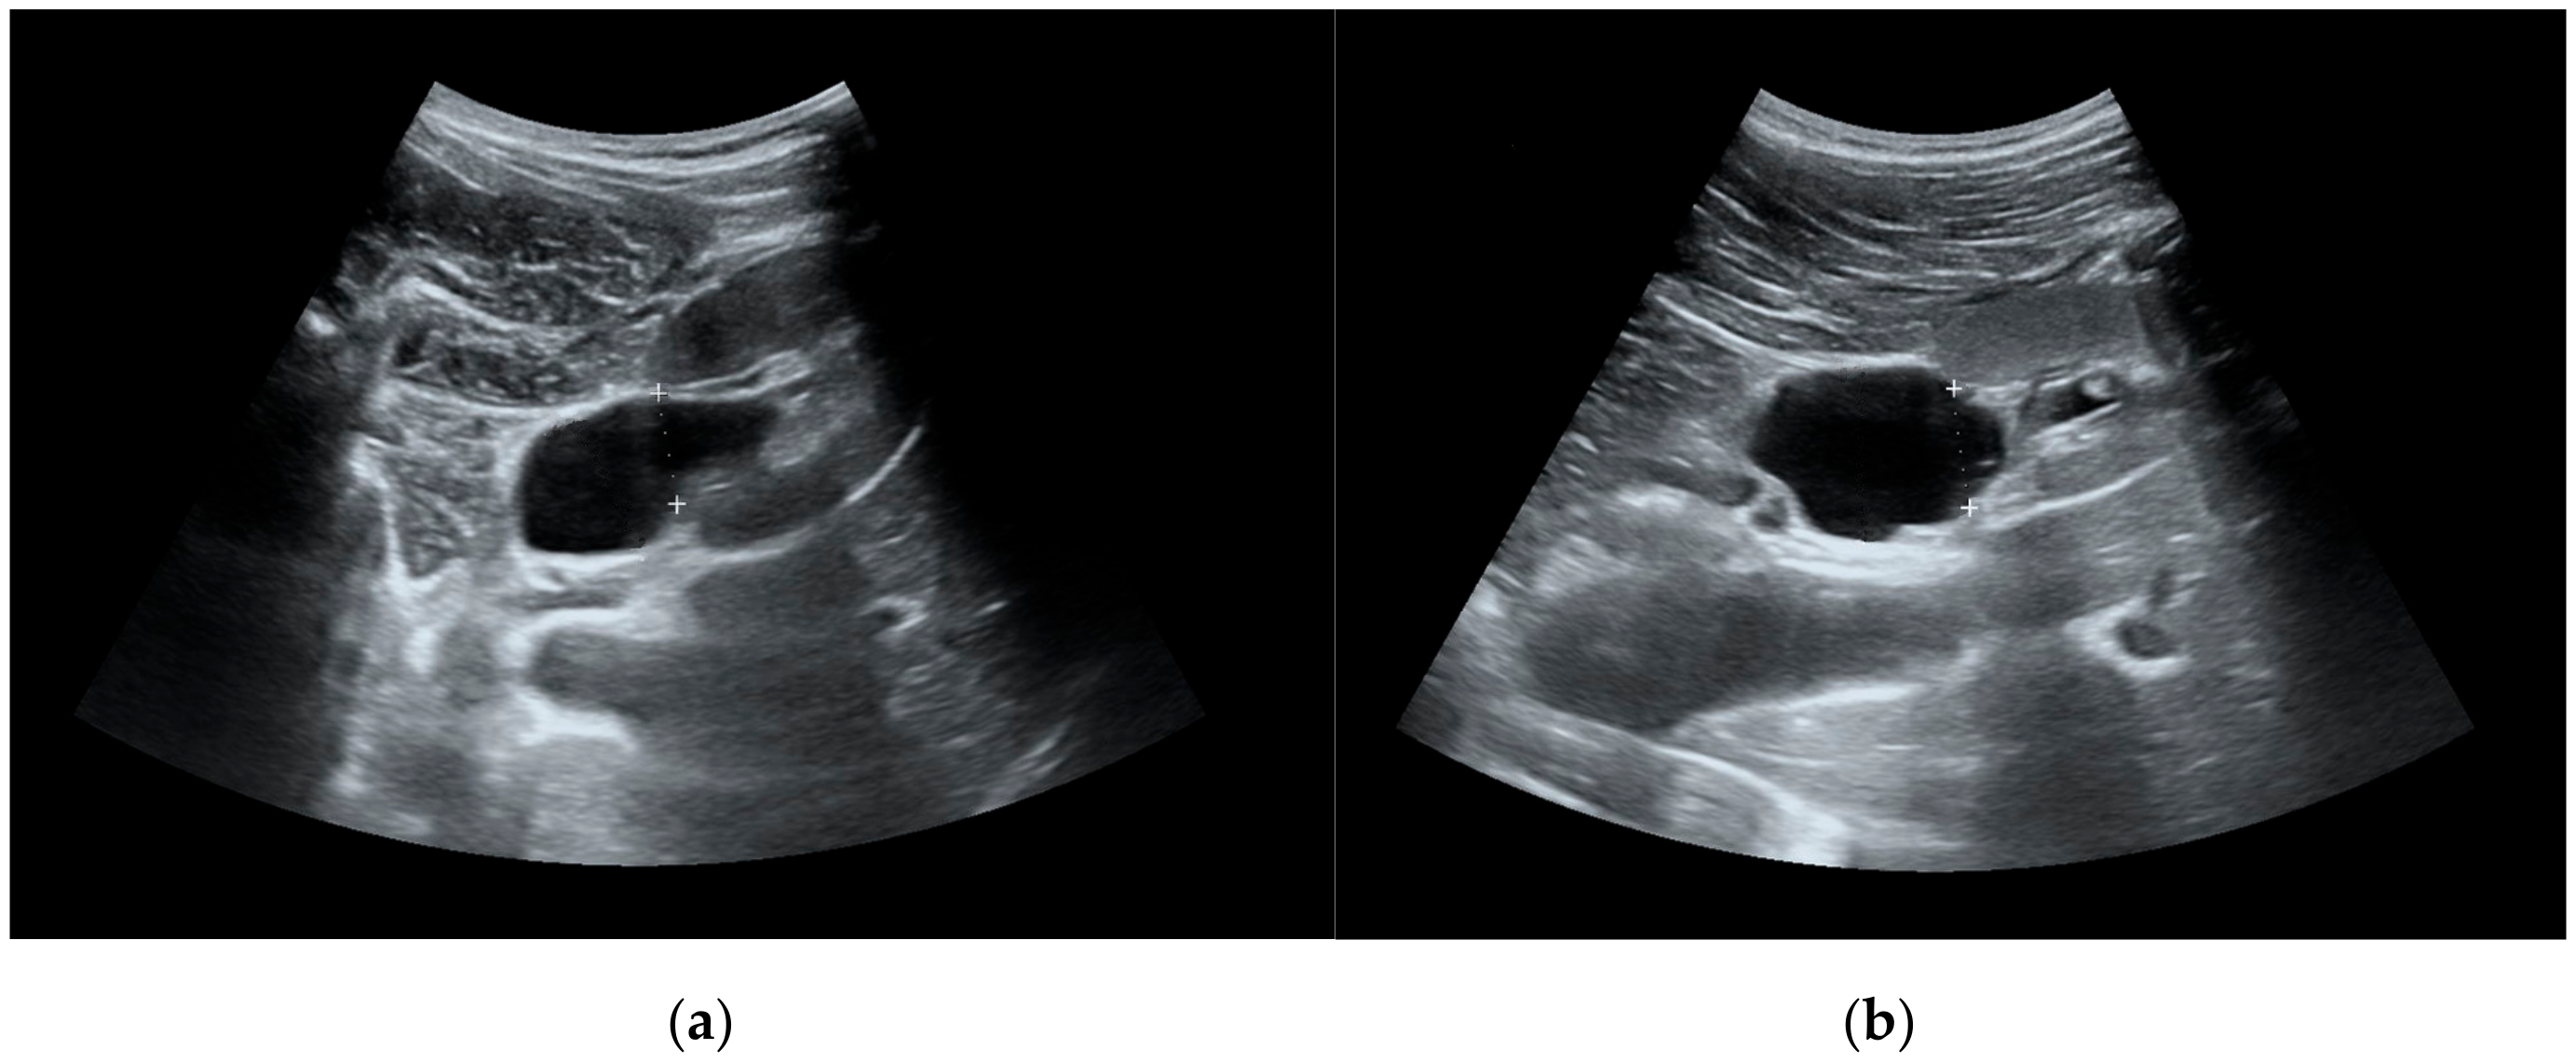

Seventy-two patients (42 males, 30 females; aged 2 months to 17 years; median age 7.07 years) with ultrasonographic diagnosis of hydronephrosis (AD cut-off value 10 mm) were included from January 2006 until October 2011 and followed for the median of 7.5 (1.5, 24) months. The linear regression model demonstrated that patient age was a confounding factor for the AD, therefore we divided patients into 3 separate groups (0–4 years, 5–9 years and 10–17 years). All children underwent a detailed clinical examination and measurement of serum urea and creatinine, and a radiological investigation including voiding cystourethrogram. Patients with reflux or neurogenic urinary bladder were excluded. A weight-adjusted dose of 1 mg/kg of furosemide was administered intravenously (maximum dose of 20 mg) after adequate oral hydration. Diuretic enhanced ultrasonography was performed in all patients only once in the beginning of follow-up. The AD of renal pelvis was measured and recorded before and at 60 min after furosemide injection. (Figure 1)

Figure 1.

(a) Renal pelvis before furosemide injection. (b) Renal pelvis 60 min after furosemide injection.